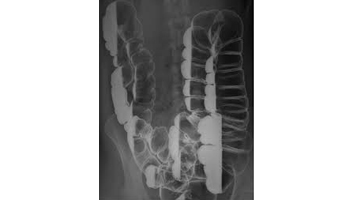

- Rx digestif : lavement baryte